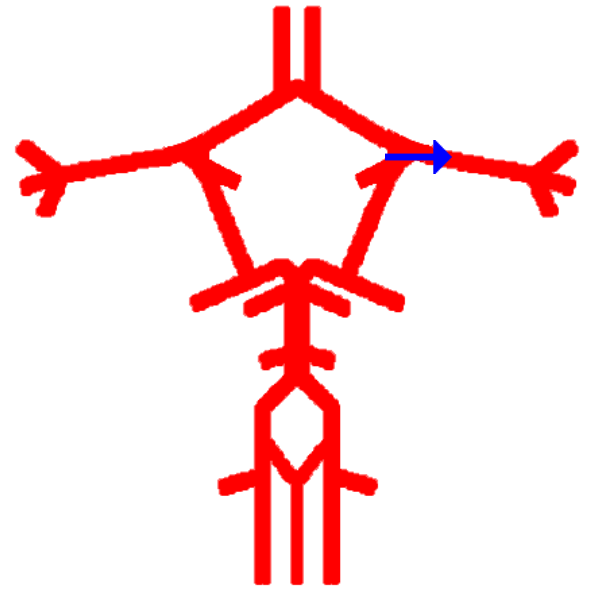

Label this cerebral artery

Middle Cerebral Artery

Label this cerebral artery

Posterior Cerebral Artery